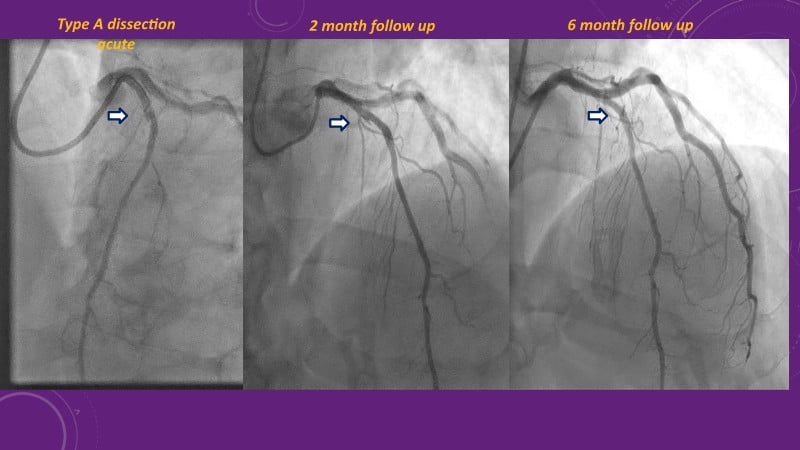

Explore cutting-edge strategies for optimizing drug-coated balloon (DCB) procedures in this session. Uncover practical tips to improve outcomes, review key indications, and examine international consensus on DCB use. Case presentations and expert discussions offer insights to refine your approach.

- To learn the tips and tricks to improve the result with drug coated balloon strategy